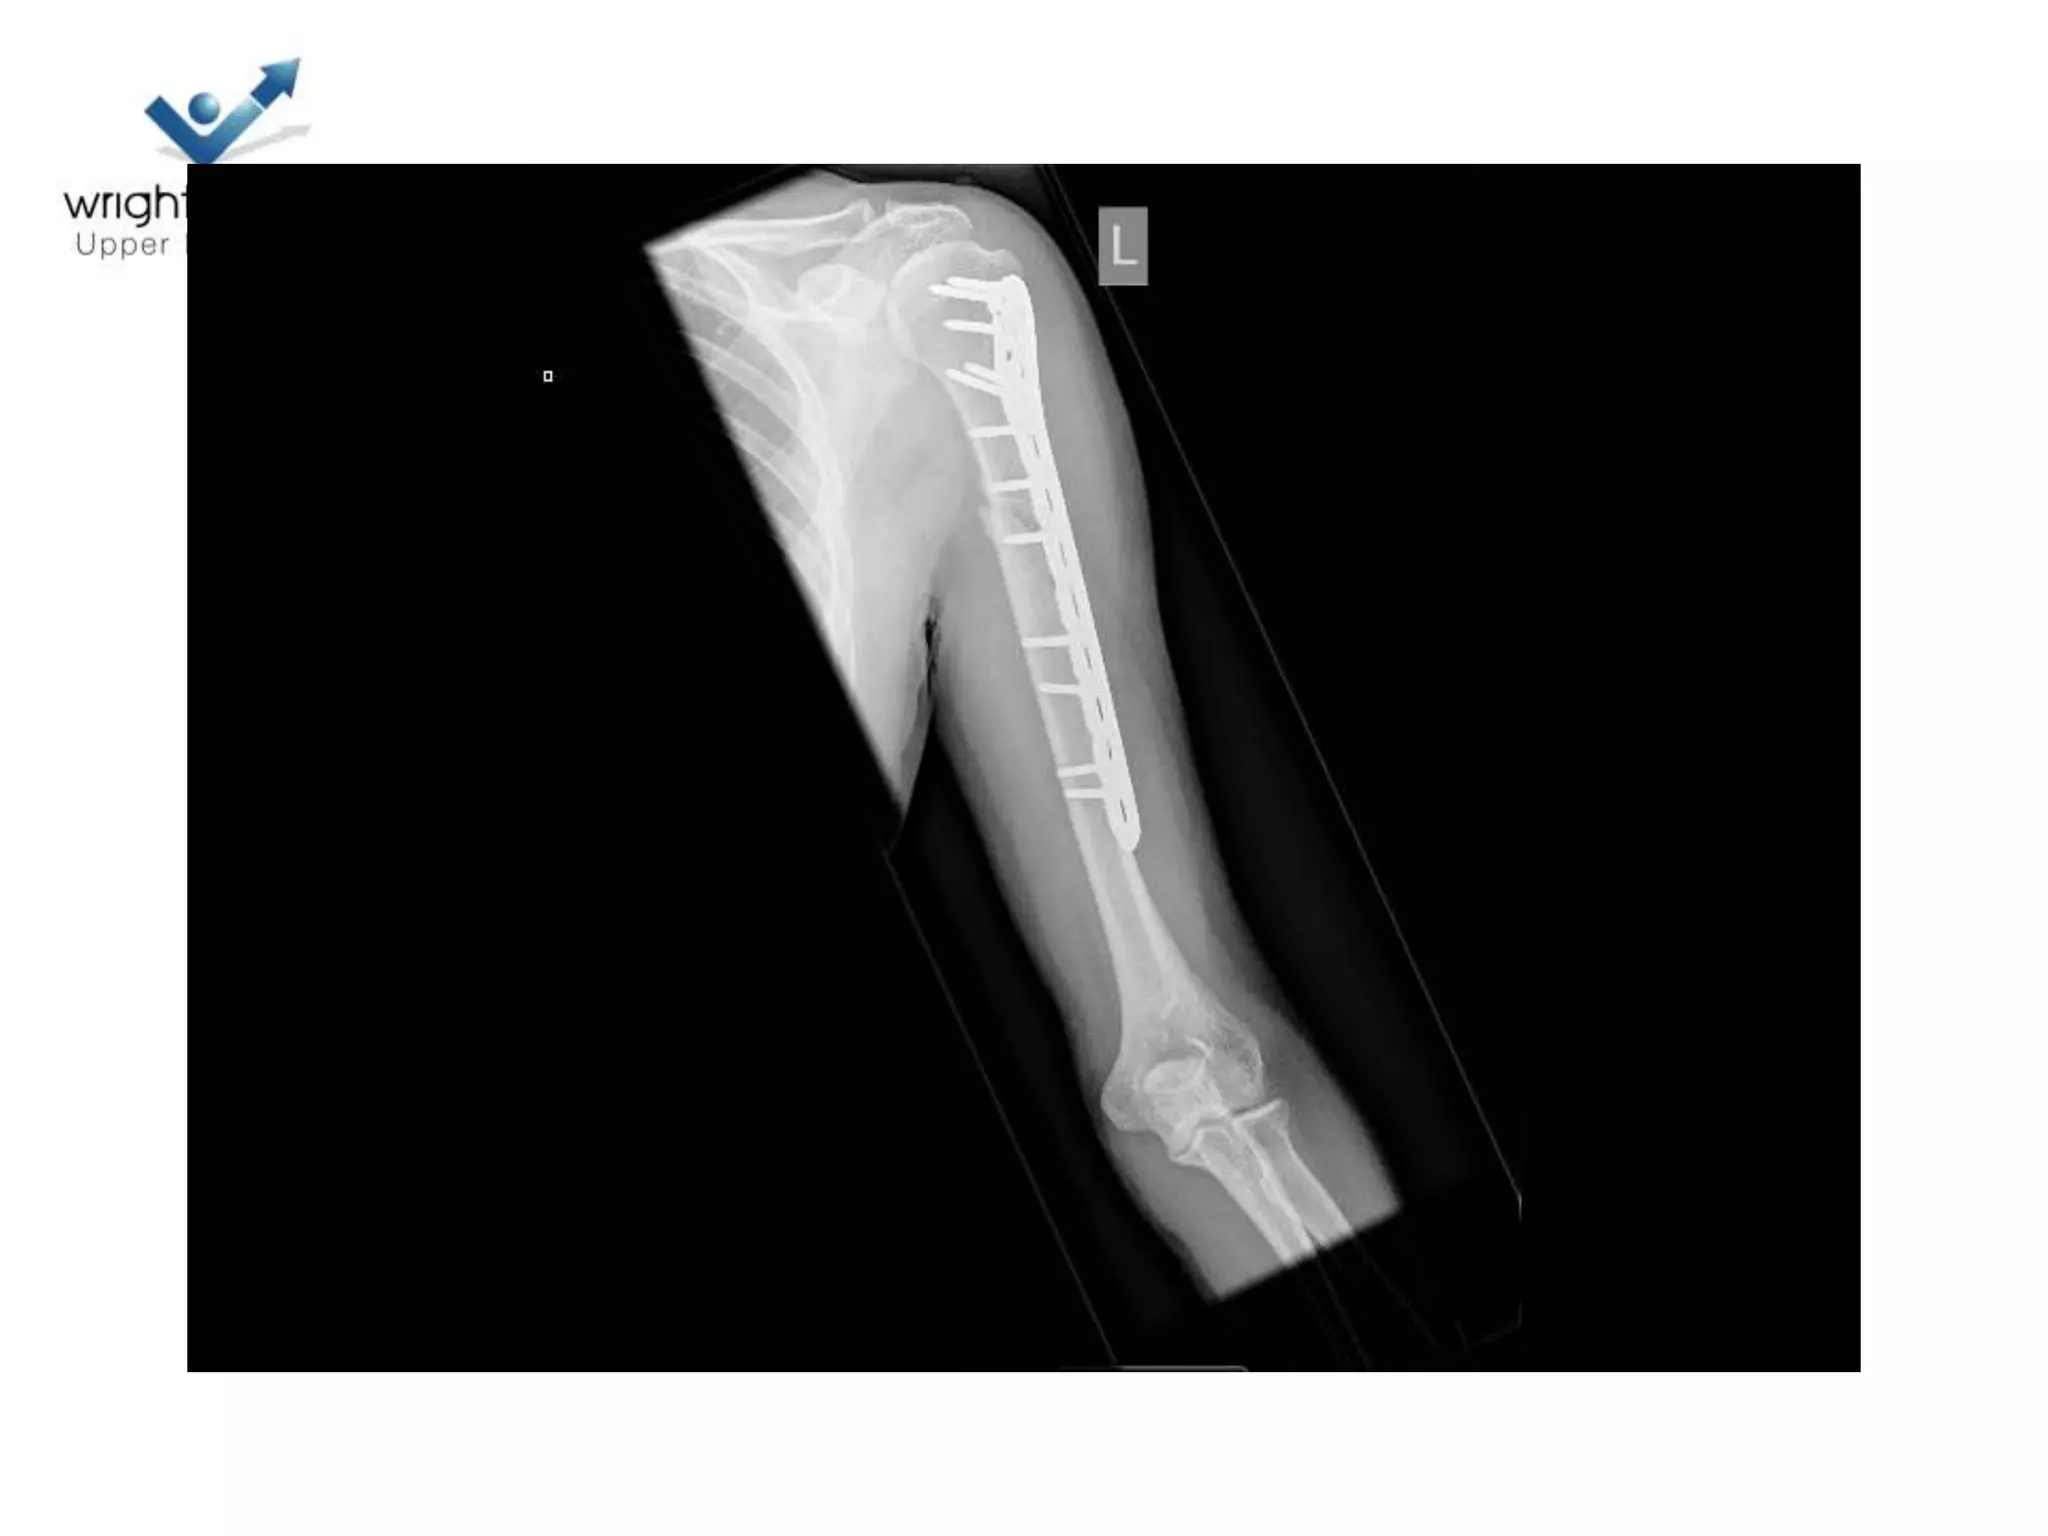

17 Polytrauma

Indications to operate

• Prevent Non union

– Shaft pulled medially